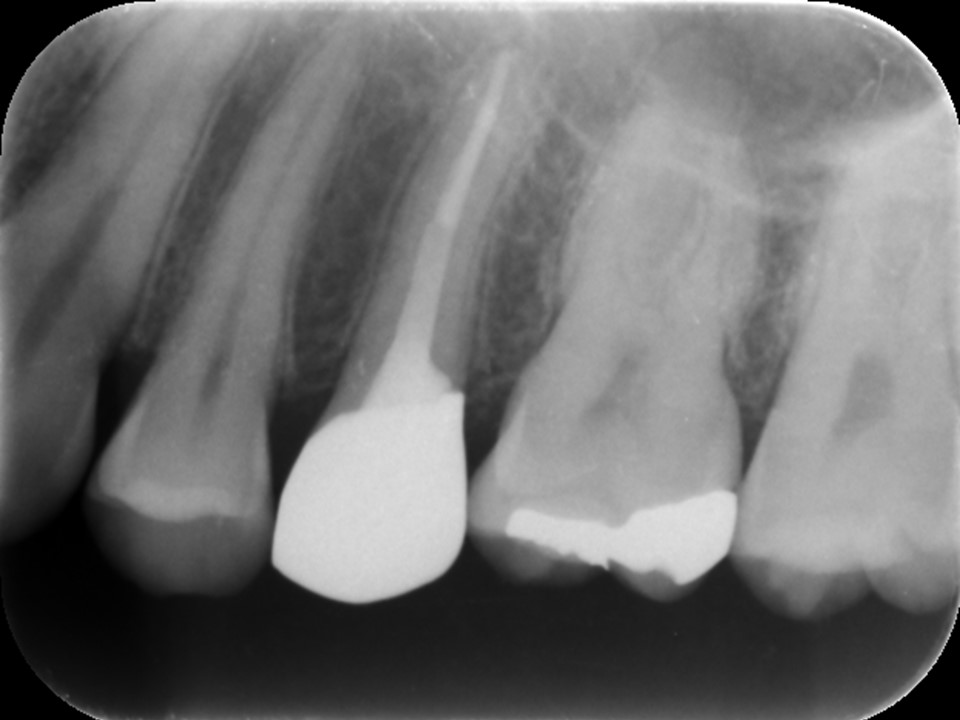

根管充填後レントゲン画像です。お薬が歯根の先端までしっかりと充填されているのが分かります。抜髄の場合、根尖部に細菌感染が及んでいないため、感染根管治療や再根管治療に比べて少ない治療回数で済むことが多いです。

根管充填後、痛みや違和感が無いことを確認し、歯冠修復を行いました。

ファイバーコアで土台を補強してからオールセラミッククラウンを被せて、すべての治療が終了です。